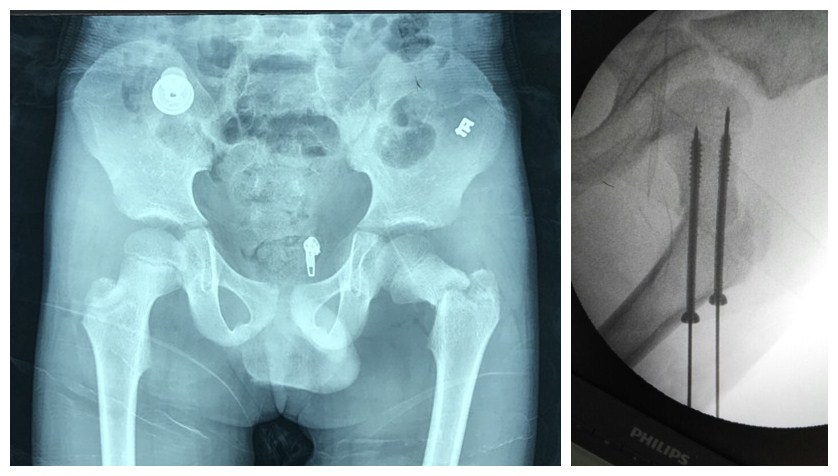

1月16日,小波被推进手术室,麻醉、连接机器人导航装置、术中C型臂透视、手法复位后,骨科机器人于远、近端分别精准钉入直径4.5mm ×长6.5cm,直径4.5mm ×长6.0cm的空心螺钉进行骨折内固定,手术非常成功。1月19日,小波术后第三天,慕明章主任带领医护团队查房,小波生命体征平稳,康复好。查房时小波的欢声笑语让我们看到儿童创伤正向着更加精准、更加微创的方向不断迈进。

采用机器人手术,定位、打钉更加精准,让手术医生有了“透视眼”,做到了“指哪打哪”,可以完成很多项徒手难以完成的操作。利用骨科机器人对小波进行微创手术治疗,实现了定位精准、软组织损伤小、手术切口小、手术安全性高的预期目标。医生在计算机上设计好钉道,系统自动计算出钉道的空间位置,机械臂将手术工具精确定位到手术位置,医生便可轻松完成螺钉的精准、安全植入。小儿骨科机器人手术精准、微创、康复速度快,将使广大患儿受益。